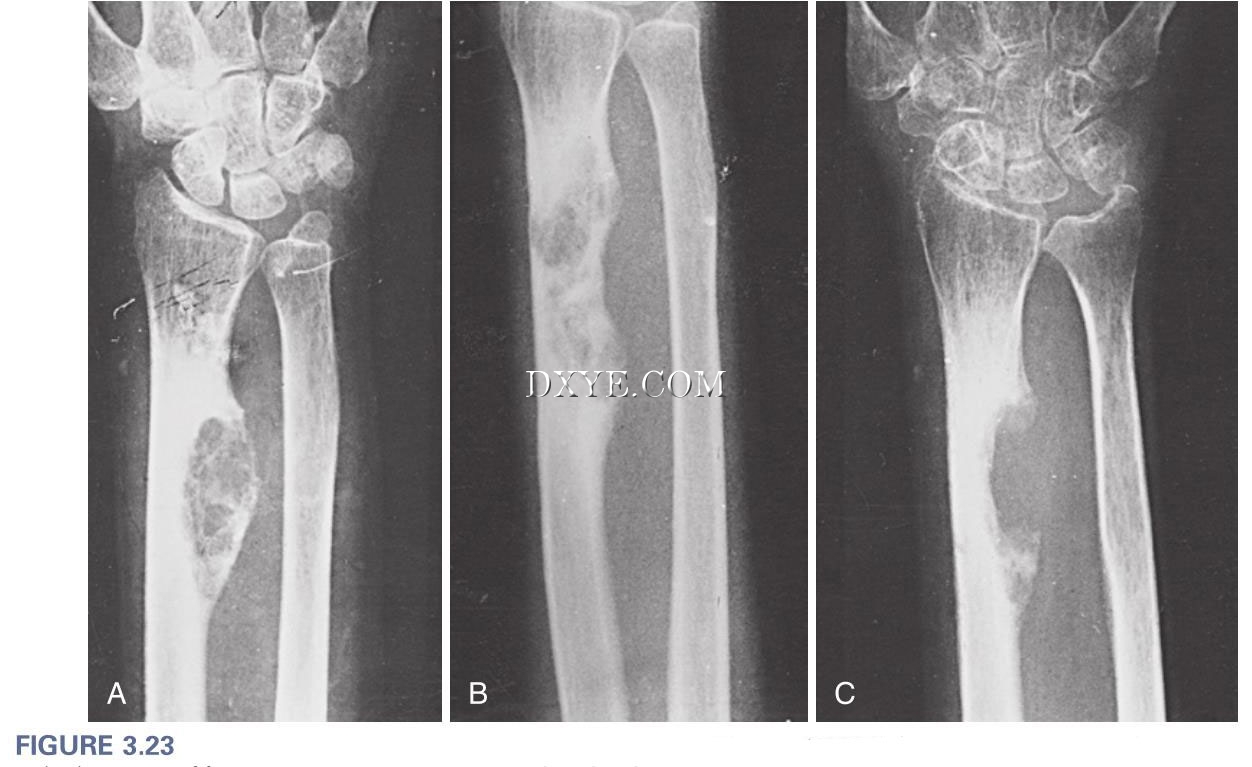

3-23.jpg

图 3.23 桡骨干结核性骨髓炎。 A, 这类似于骨的肿瘤性病变,有骨质破坏和培养结核分枝杆菌。 B, 混合性囊性硬化型。 C, 口服抗结核化疗后,病变愈合并复发。 (Courtesy of S. M. Tuli, New Delhi, India.)